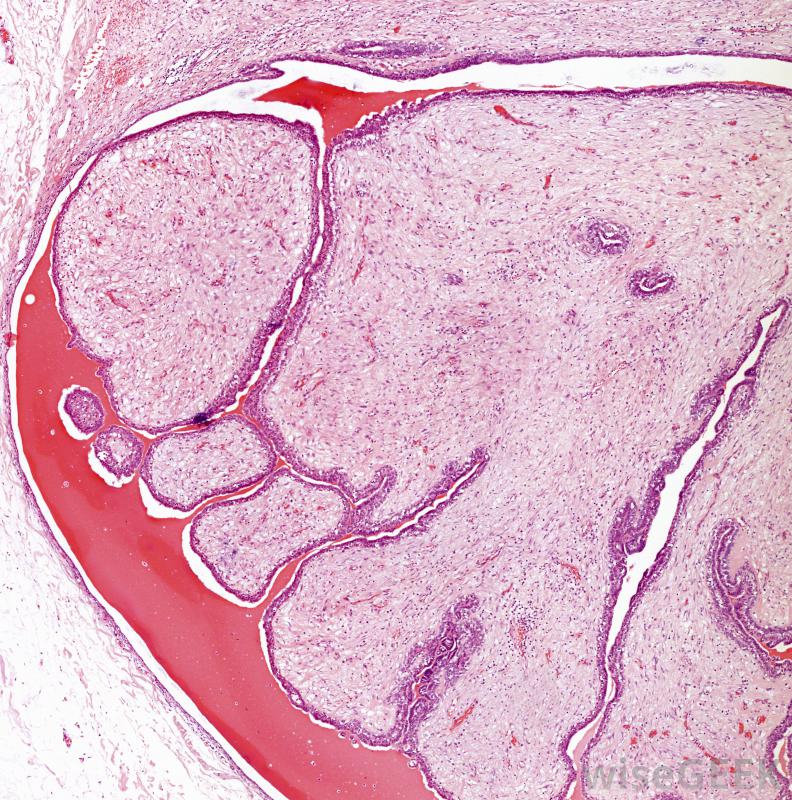

乳腺腺瘤,又称纤维腺瘤,是女性乳腺组织中形成的良性肿瘤。这种非癌性生长最常见于尚未绝经的年轻女性,随着年龄的增长,其大小和形状可能会发生变化。为了诊断这种情况,通常使用与诊断乳腺癌相似的检查方法,因为肿瘤的外观和感觉都是一样的。

典型的腺瘤直径只有几厘米当女性患上乳腺腺瘤时,通常一个乳房会有一个单一的肿瘤。有时,可能不止一个,但它们通常大小相似,可能不在同一个乳房内。唯一的症状通常是在进行常规自我检查或进行乳房X光检查时发现肿块,因为它通常不会引起疼痛。大多数患这些良性肿瘤的妇女在20至30岁之间都会发生这种情况乳腺腺瘤可能与激素变化有关,典型的肿块只有少数直径厘米,但如果妇女怀孕可能会变大。肿块通常是球形的,当按压时,会在乳房组织内自由移动乳腺腺瘤的存在并不是乳腺癌发生的前兆,尽管已经发现这种情况可能表明在以后的生活中患恶性肿瘤的风险稍高一些。复杂的乳腺腺瘤,当有一个以上的肿瘤存在时,可能会稍微增加乳腺癌的风险,而单一的良性肿瘤尚未发现与任何其他健康并发症风险的增加有任何关联。

乳腺纤维腺瘤是一种在女性乳腺组织中形成的良性肿瘤这些肿块很少在绝经期妇女中形成,因为乳腺腺瘤在年轻妇女中更常见,而且肿块在怀孕和哺乳期间会发生变化,有人怀疑这些肿瘤的生长与生殖系统激素的产生有关。一些妇女发现肿瘤的大小随着年龄的增长而减小,尽管它们通常不会完全消失。